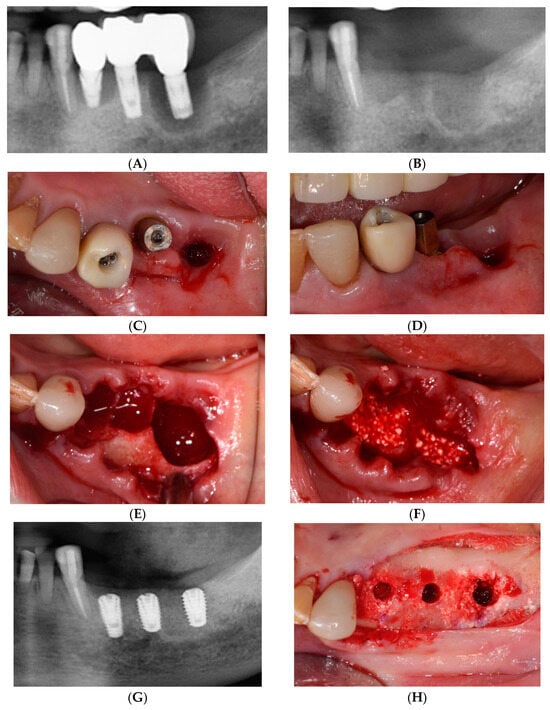

2.1. Surgical Procedures of the Simplified Free Gingival Graft Using Fixation Tacks (sFGG)

2.2. Case